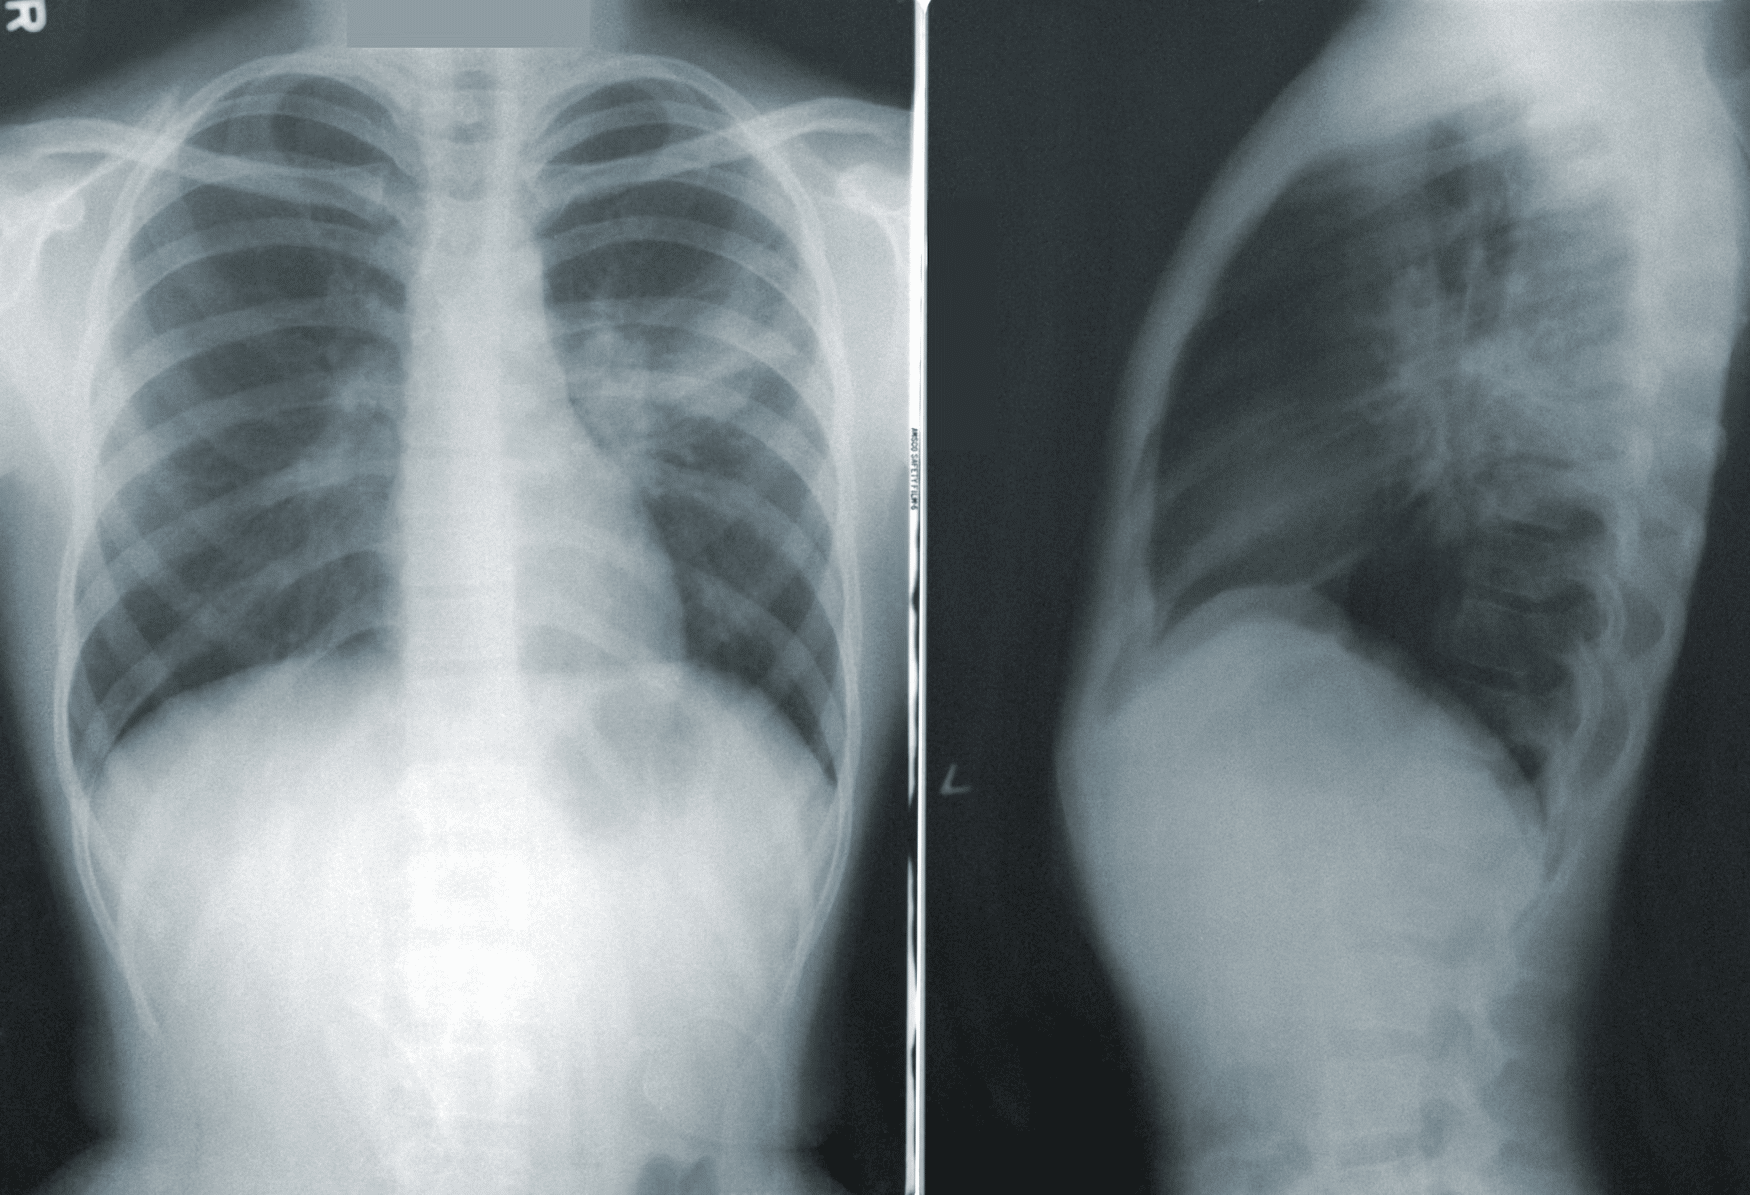

Přesná příčina bolesti se občas zjišťuje těžko. Doma to s jistotou ani nejde, protože je na to potřeba provést pár vyšetření. Doktor vás možná pošle na rentgen, aby odhalil případné zlomeniny nebo problémy s kostmi. Ultrazvukem potom může vyšetřit šlachy a svaly. Dál se můžete dostat na magnetickou rezonanci (MRI), která poskytuje detailnější zobrazení měkkých tkání. V případě podezření na nervové poškození vás nejspíš pošlou na elektromyografie (EMG), to měří elektrickou aktivitu svalů.